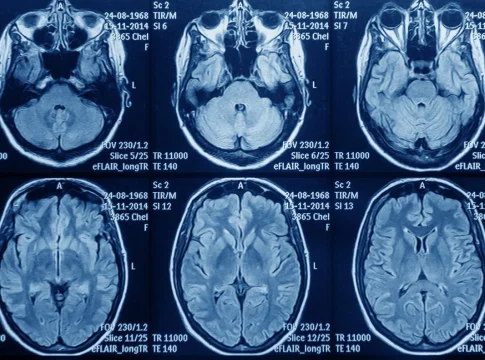

Según explicó Astuce, el glioblastoma es el tumor cerebral más agresivo y con peor pronóstico, con una mediana de supervivencia de apenas 14,6 meses con el tratamiento estándar, que combina cirugía, radioterapia y quimioterapia con temozolomida. A pesar de este pronóstico, el estándar de tratamiento ha permanecido estático en España durante más de dos décadas.

Sin embargo, en los últimos años, estudios clínicos han demostrado que el uso de TTFields, un dispositivo que emite campos eléctricos para frenar la proliferación de las células cancerosas, puede aumentar significativamente la supervivencia cuando se combina con la quimioterapia de mantenimiento. De hecho, las guías internacionales (NCCN) y nacionales, incluyendo las de la Sociedad Española de Oncología Médica (SEOM) y el Grupo Español de Investigación en Neurooncología (Geino), recomiendan la incorporación de los TTFields como parte del estándar de tratamiento del glioblastoma de nuevo diagnóstico.